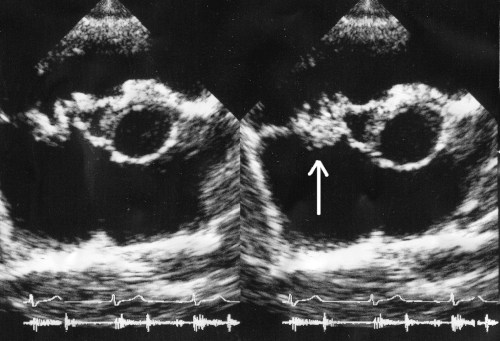

| Vegetation of tricuspid valve by ECHO | |